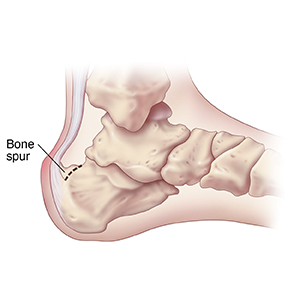

Spur on the back of the heel

The heel spur is removed, and the Achilles tendon is repaired. Your foot will be placed in a cast. To keep you from bearing weight on this foot, you will need crutches for several weeks.